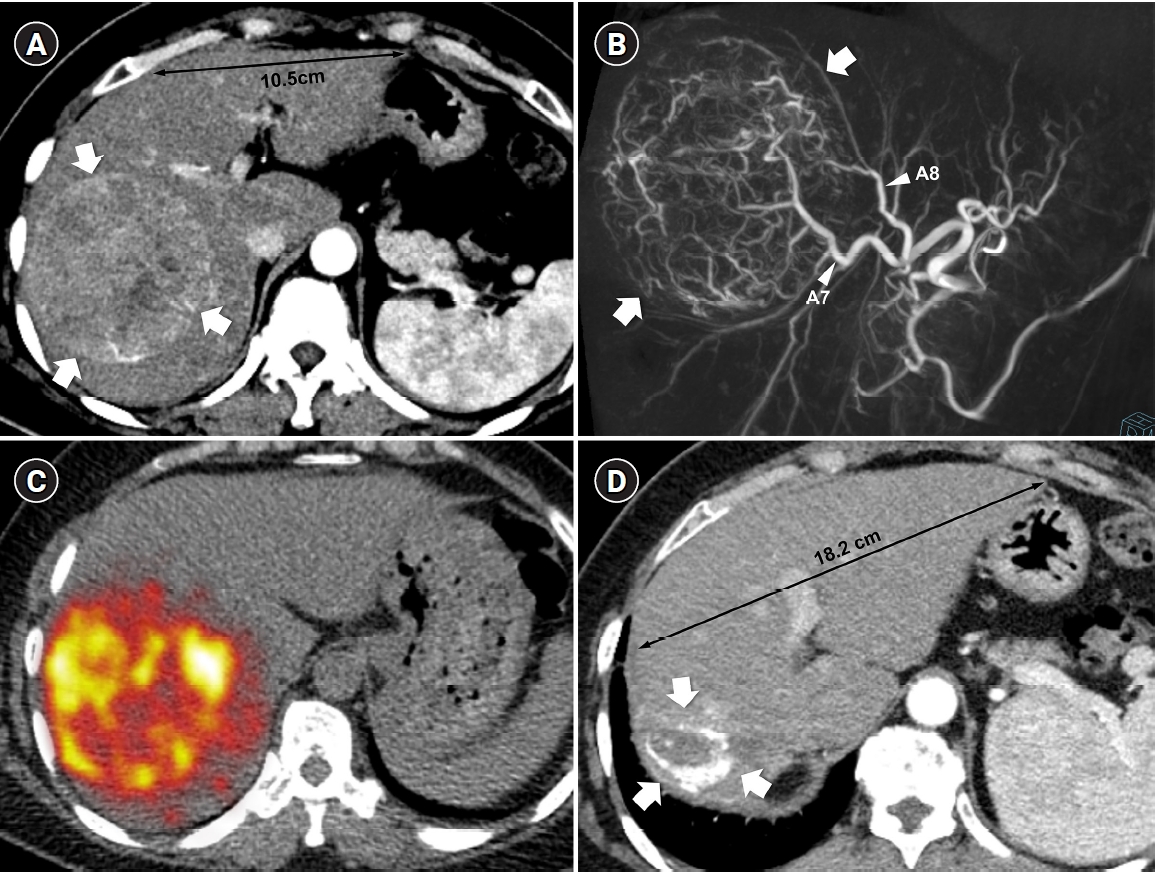

Fig. 2.

Fig. 2. Radiation major hepatectomy in a 60-year-old woman with hepatocellular carcinoma. (A) Contrast-enhanced computed tomography (CT) shows a 9.0-cm hypervascular tumor (arrows) with two satellite nodules (not shown) in segments 7 and 8. (B) Cone-beam CT hepatic arteriography shows tumor staining (arrows) supplied by A7 and A8 (arrowheads). A total of 9.11 GBq of glass microspheres was infused via A7 and A8. (C) Post-treatment Y-90 positron emission tomography shows intense uptake throughout the tumor, consistent with complete microsphere coverage, with a perfused liver dose of 355.3 Gy and a tumor dose of 609.9 Gy. (D) Fifty-month follow-up CT shows complete response with dystrophic calcification (arrows), atrophy of segments 7 and 8, and compensatory hypertrophy of the left hepatic lobe (double arrowheads).